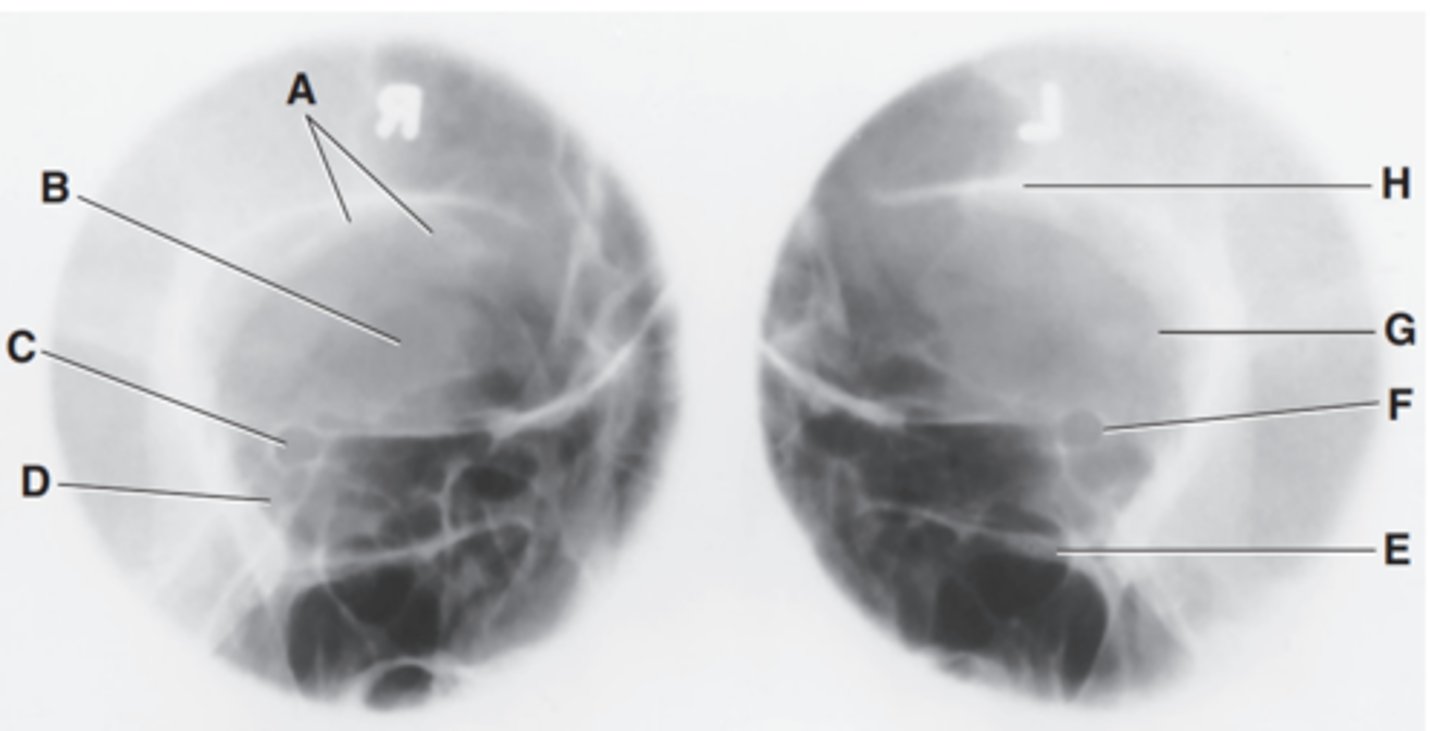

Label A

Body of maxilla

Label B

Bony nasal septum

Label C

Anterior nasal spine

Label D

Zygomatic arch

Label E

Coronoid process

Label F

Condyle

Label G

Mastoid process of temporal bone

Label H

Angle of mandible

Label I

Foramen magnum

Label J